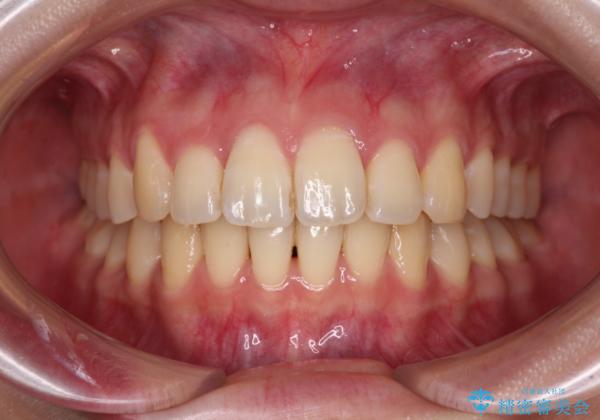

奥歯の咬み合わせはしっかりと改善され、前歯の突出感も改善されました。